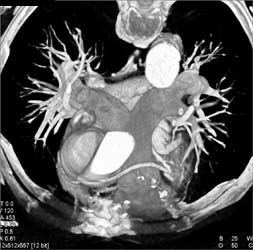

Pulmonary Embolism